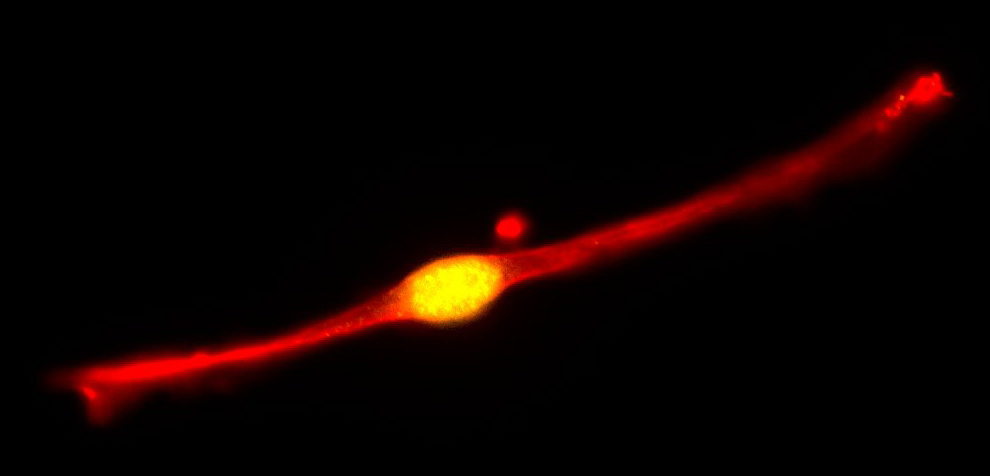

Molecular biologist Gabi Gerlitz of Ariel University studies what happens to the nucleus of melanoma cells during migration, a key step in metastasis. The nucleus of every cell holds its genetic material, the chromosomes.

When melanoma cells migrate, they squeeze themselves to pass through blood vessels or tissues. Squeezing condenses the chromosomes inside the nucleus, causing both physical and genetic changes that enable migration.

Gerlitz’s lab showed in mouse studies that interfering with condensation in the nucleus successfully interferes with migration. Ongoing studies look for factors at the nuclear envelope that affect chromosome condensation and cell migration.